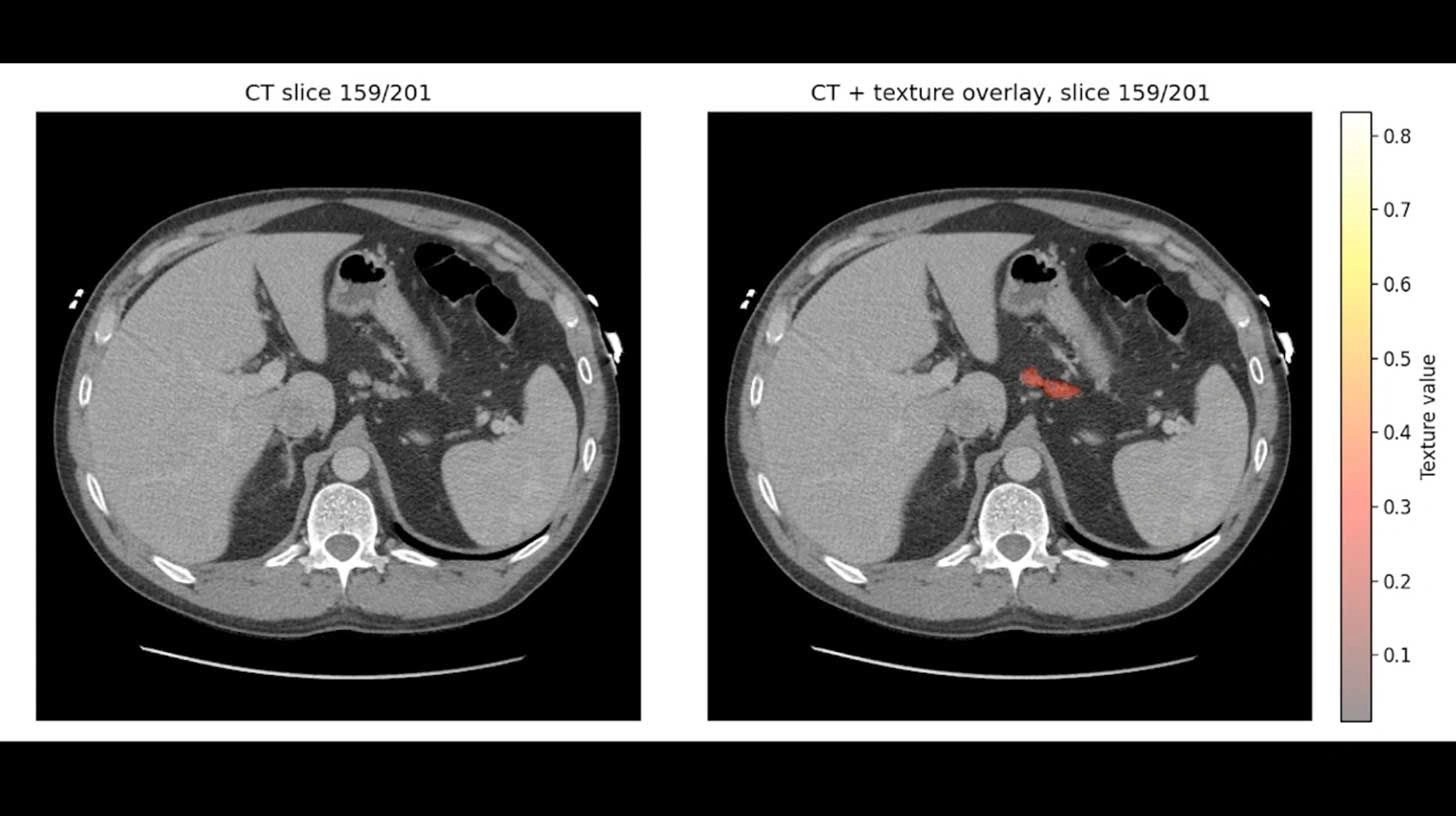

REDMOD stands for Radiomics-based Early Detection Model. Rather than looking only for a visible tumor, it analyzes subtle quantitative patterns in the pancreas that may signal early disease.

Mayo Clinic says the system measures hundreds of imaging features, including:

- Tissue texture

- Structural patterns

- Quantitative radiomic signals

- Early biological changes that may not be visible to radiologists